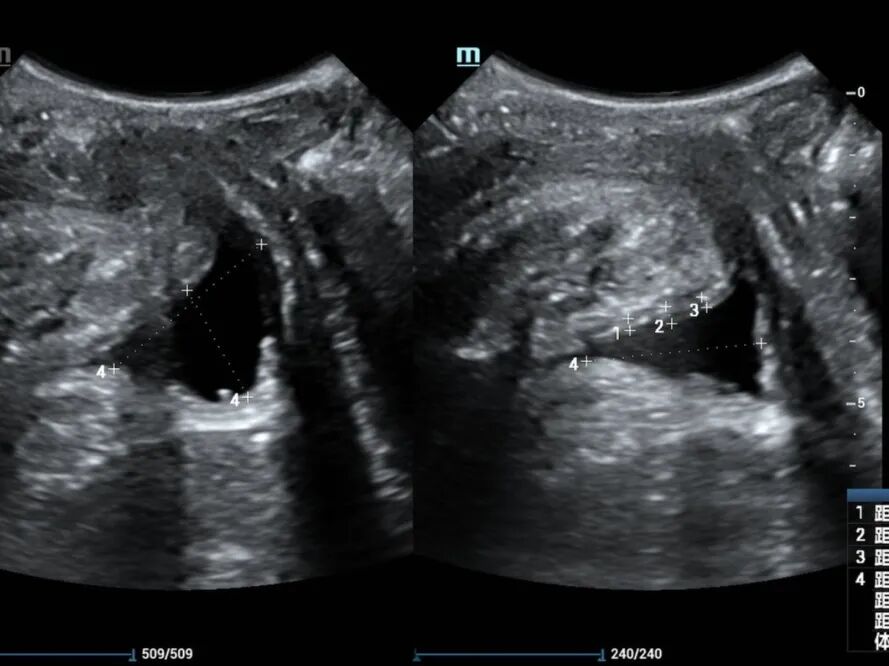

近日,54岁的黄女士因“尿失禁13年”来我院妇女保健科就诊,黄女士讲述了近十年来经常发生尿频尿急憋不住尿的经历,自己咳嗽、大笑或者长时间走路后便出现漏尿等尴尬症状,严重影响正常生活和社交活动。由于涉及隐私部位,怕人笑话,一开始她不敢跟身边的人说起这件事,能忍则忍。最近随着症状加重,难以忍受,终于来我院就诊。 在妇女保健科医师颜惠芳建议下,黄女士前往我院超声医学科行四维盆底超声检查,检查后发现黄女士有膀胱脱垂、子宫脱垂的现象,诊断为“压力性尿失禁”,终于找到漏尿的原因了,黄女士的治疗也可以针对性开展。 现实生活中,不少女性朋友也有过这样尴尬的经历,大笑、打喷嚏、咳嗽时尿液溢出外出时总想找厕所,私密处总有异物感,腰酸背痛,下腹坠胀,夫妻生活不和谐……种种难言之隐羞于说出口,却又如影随形。这一切的罪魁祸首很可能是——盆底功能障碍。 一、什么是盆底功能障碍 盆底功能障碍是指盆底肌肉、筋膜、韧带等支持结构受损而导致的一系列临床症候群,如压力性尿失禁、子宫等盆腔脏器脱垂、粪失禁、梗阻型便秘和性功能障碍等。妊娠和分娩是造成此病的首要原因,其中以经阴道分娩危险性最高,当前已成为影响全球妇女身心健康的五种最常见疾病之一,被称为“社交癌”。 二、为什么会发生盆底功能障碍? 怀孕、分娩、衰老、肥胖、长期便秘、慢性咳嗽、长期提重物等原因,都会导致盆底肌损伤,分娩是造成盆底肌损伤的主要原因。 通常胎儿头部大小都会大于正常的阴道大小,分娩时,阴道会受到胎儿头部的挤压而扩张,造成盆底肌肉损伤。双胎、巨大儿、分娩两次及以上的妈妈们,盆底肌受到的损伤通常会加倍。产后和围绝经期为高发期,被称为严重影响女性生活质量的五大慢性病之一。 三、什么是盆底超声? 盆底超声是使用特殊配置的超声仪器,利用二维图像、三维重建、动态四维显示联合应用,在患者静息、缩肛、valsalva不同状态下,直观了解盆底的静态、动态结构、显示耻骨联合、尿道、膀胱、阴道、宫颈、直肠壶腹及肛管等结构,从而评估盆底各脏器位置、功能,脏器脱垂情况、盆底肌有无损伤等。 盆底超声适应症: 1.盆腔脏器脱垂:膀胱脱垂、子宫脱垂、直肠膨出等; 2.排尿异常:压力性尿失禁、尿潴留、排尿困难等; 3.排便异常:粪失禁、便秘等; 4.性功能障碍:性交痛、性欲降低等; 5.慢性盆腔痛:下腹部疼痛、腰骶部或会阴痛等; 6.产后女性(42天至6个月)盆底功能障碍的早期筛查。 可疑盆底功能障碍性疾病人群、产后复查及围绝经期女性均建议行盆底超声检查。 超声医学科盆底超声检查介绍 我院超声科自2019年开展该项技术以来,已为500余名女性患者完成盆底超声检查。竭诚欢迎有需要的女性市民朋友来电咨询(025-56232058)或前往我院妇女保健科门诊就诊。 盆底超声检查时间:每周一和周二下午(具体以预约安排为准) 盆底超声检查医师简介 褚爱萍 科室副主任,主任医师(资格)。南京超声学会介入与腹部学组委员,从事超声诊断十余年,曾先后于江苏省人民医院及中大医院进修学习,并承担临床教学工作多年,擅长心脏、血管等超声诊断,对腹部、妇产、盆底、浅表、肌骨等亦有丰富的超声诊断经验。 汪金 中国共产党员,副主任医师,医学硕士,先后在四川大学华西医院、重庆医科大学附属儿童医院、北京301医院、朝阳医院等多家三甲医院进修、培训学习,取得了超声产前筛查、盆底超声、输卵管超声造影、肿瘤消融治疗等多项技术资质。 获省妇幼新技术引进三等奖,主持及参与省市级课题3项,发表论文数篇,其中SCI 3篇,授权国家专利9项。 钱露 副主任医师(资格),硕士研究生。毕业于徐州医科大学医学影像专业。从事超声诊断工作十余年,熟练掌握各种常见病、多发病的超声诊断,擅长妇科超声、盆底超声、产前筛查超声等工作。 李诺 主治医师,毕业于徐州医科大学临床医学专业,从事超声诊断工作数年,熟练掌握各种常见病,多发病的超声诊断工作,擅长妇科超声,盆底超声等超声诊断工作。